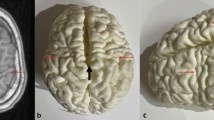

The models were randomly placed onto a table and numbered from 1 to 12 for viewing by study participants, who were recruited from the local research and clinical environment of the principal investigator (A.C.), in South Africa. Representative MR images and the corresponding 3-D printed models of three cases are shown in Figs. 1, 2, and 3.

Images of an 11-year-6-month-old girl presenting with cerebral palsy. a, b Axial (a) and sagittal (b) T1-weighted magnetic resonance images show localized perirolandic atrophy and signal change (red arrows) and lentiform separation of the cerebral hemisphere (white arrow). c Vertex (c, d) and lateral oblique (d) 3-dimensional printed models with accurate depiction of the lentiform separation (white arrow) and perirolandic atrophy (black arrows)

Images of a 2-year-2-month-old boy with cerebral palsy due to term partial prolonged hypoxic ischemia. a–c Axial (a), coronal (b) and sagittal (c) T1-weighted magnetic resonance images of the brain and (d–f) vertex (d), posterior (e) and left (f) side views of the corresponding 3-dimensional (D) printed model of the brain. Images show areas of injury with cortical atrophy (red arrows) clearly appreciated on the 3-D models, lentiform separation of the cerebral hemispheres (black asterisks) due to cerebral atrophy and volume loss in the parasagittal watershed regions, widening of the Sylvian fissure (black arrow) due cerebral atrophy and volume loss and relative sparing of the left anterior intervascular watershed (red asterisk)